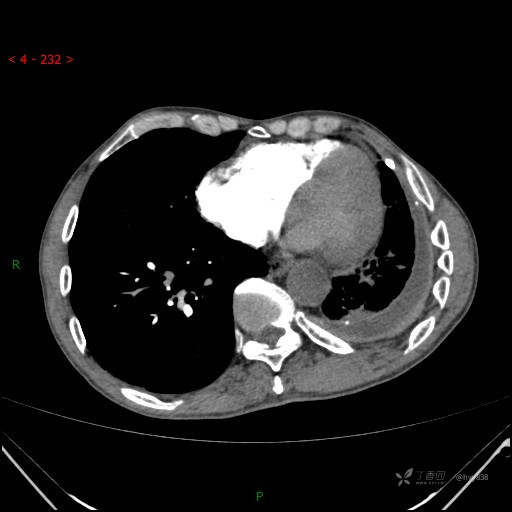

增强动脉期